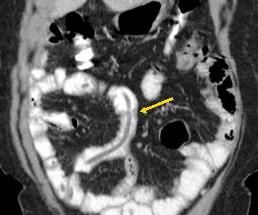

Treatment was initiated with ciprofloxacin and flagyl for a presumed infectious colitis. Because of the cecal findings, the patient was admitted for possible appendicitis. Results of a subsequent CT scan showed large worms in the distal jejunum and ileum (Figures 1-4). Stool samples were sent for an ova and parasite (O&P) test. The patient improved and was discharged home.

Figure 2